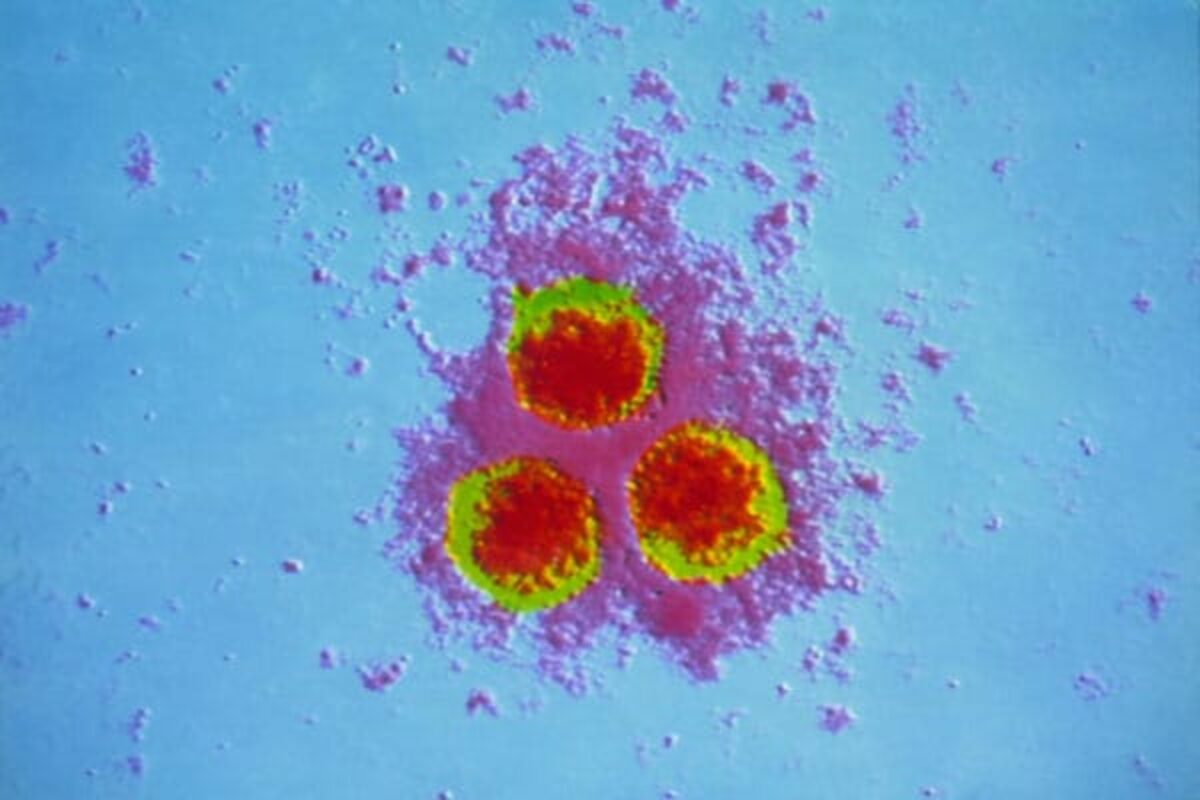

Медицинские снимки и изображения опоясывающего герпес вируса

Раздел: Фотодневник открытий